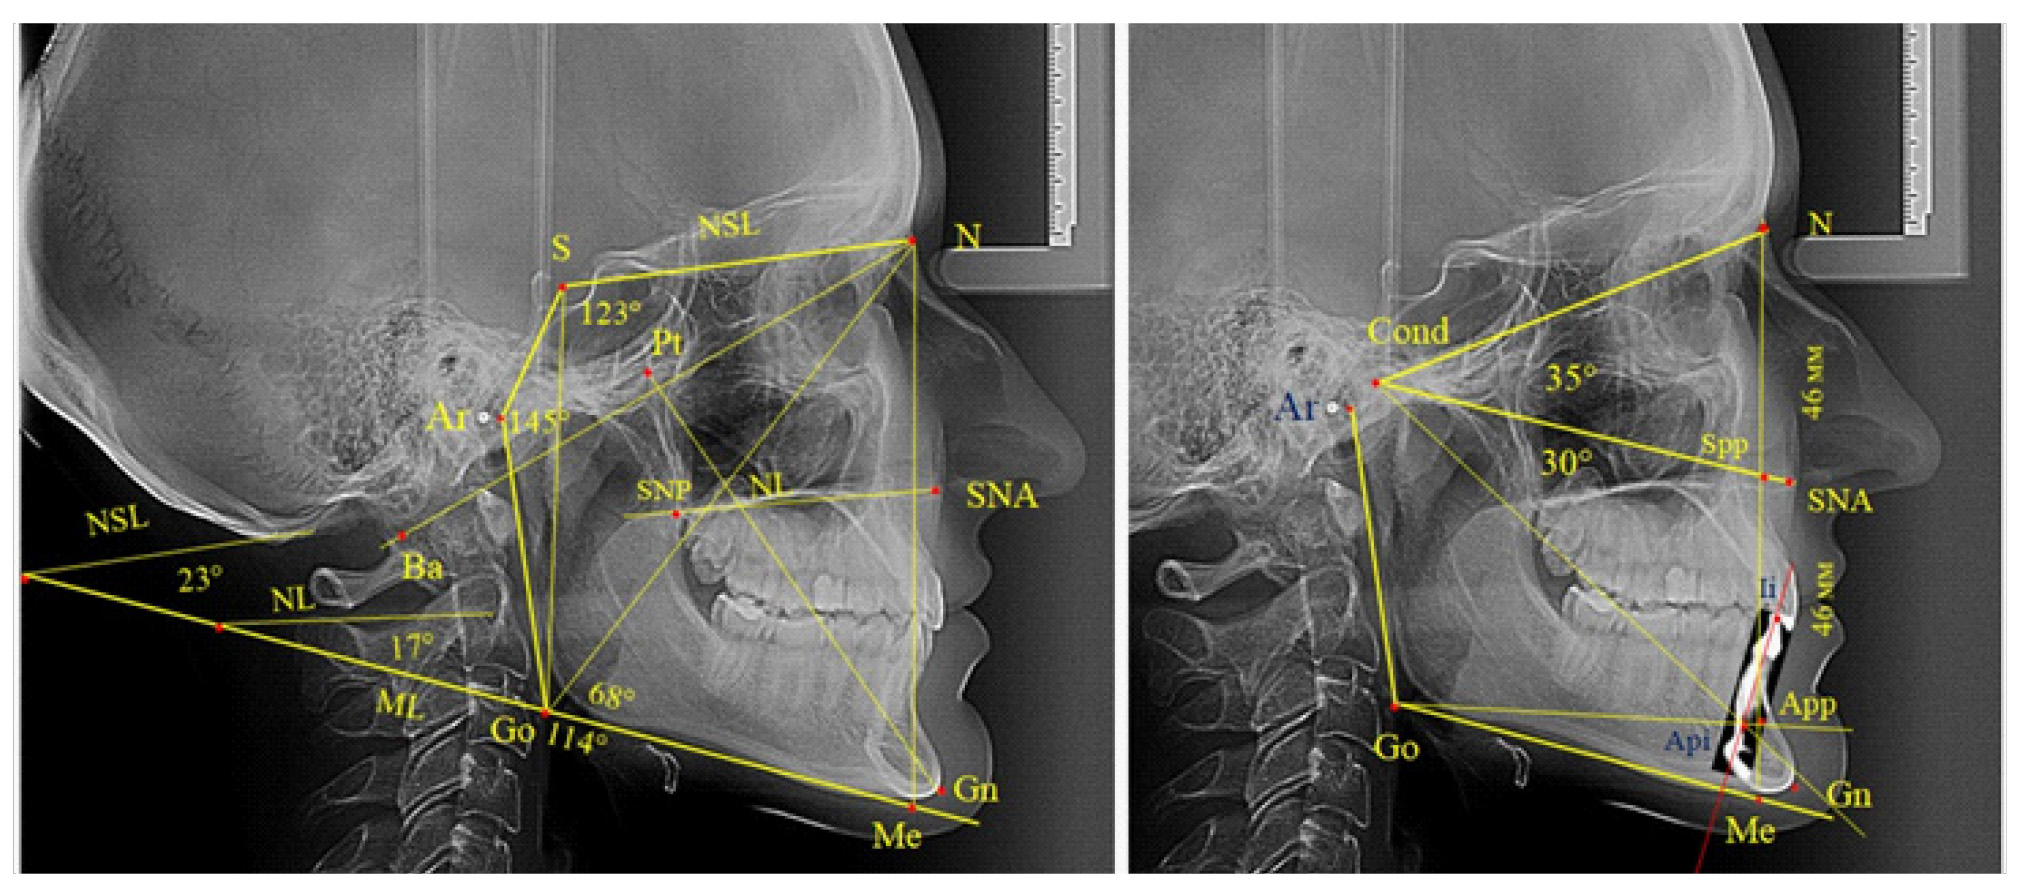

Основу анализа традиционно составляла суммарная составляющая трех углов Bjork, которая включала углы N-S-Ar, S-Ar-Go и Ar-Go-Me, которые ограничивают костные структуры линевого отдела головы, и полученная величина определяет типологические особенности роста лица. Нижний нижнечелюстной угол образован линиями N-Go и Go-Me. При построении лицевого угла Ricketts проводили линию N-Ba и линию Pt-Gn, с последующим измерением внутреннего угла.

Также к показателям типа роста относили углы, образованные мандибулярной плоскостью, с линией основания черепа (NSL-ML) и основания верхней челюсти (NL-ML). Кроме определения угловых параметров оценивали линейные показатели, в частности проводили сравнение передней высоты лица (N-Me) с задней высотой (S-Go).

Данная методика позволяла определять положение верхушки корня медиального нижнего резца, полученный ориентир в ортодонтии принято обозначать как Api (apicalе inferior), а точка режущего края нижнего резца обозначалась как Ii. Для оценки вертикальных параметров оценивали угол N-Cond-SNA, который использовали для определения параметров назального отдела. При этом точка Cond соответствовала верхнему полюсу суставной головки. Угол SNA-Cond-Api определял угловые параметры гнатического отдела лица без учета размеров подбородка, который является наиболее вариабельной структурой нижней челюсти. Альвеолярную часть нижней челюсти отделяли от подбородочной части линией, соединяющей конструктивную точку угла нижней челюсти Go с верхушкой корня нижнего резца (Go-Api).

Вертикальная линия передней высоты лица (N-Me), после ее пересечения с линией Cond-SNA, определяла положение точки Spp, при этом вертикаль N-Spp использовалась в качестве оценки высоты назального отдела лица. Продолжение линии Go-Api до пересечения с линией N-Me позволяла определить положение конструктивной точки Арр и оценить линейные размеры гнатической части лица по величине вертикали Spp-Арр (рис. 1).

Рис. 1. Методы оценки основных параметров ТРГ для определения вертикальных размеров лицевого отдела головы